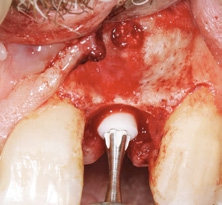

Extraoral wurde das explantierte Implantat auf Vollständigkeit geprüft, indem die beiden Teile passgenau aufeinandergelegt wurden (Abb. 6). Nach sorgfältiger Kürettage, intensiver Spülung und Dekontamination der Defektstelle wurde das prothetisch orientierte Implantatlager mit den entsprechenden Formbohrern für das CERALOG Hexalobe Implantat (12 mm L, 4 mm Ø) über den bestehenden Implantatfundus hinaus apikal aufbereitet (Abb. 7). So konnte eine ausreichende Primärstabilität des Implantats erzielt werden. Um einen ausreichenden Knochen-Implantat-Kontakt zu erreichen, musste der Stollen mit einem Gemisch aus autologen Knochenspänen und Bio-Oss Collagen (Geistlich) vor der Insertion augmentiert werden (Abb. 8) [15]. Das Implantat wurde mit dem Eindrehinstrument aus dem Blister genommen und manuell in das Knochenfach inseriert. Das Implantat erreichte eine Primärstabilität von 20 Ncm. Das Design der Innenkonfiguration trägt dem Material Zirkoniumdioxid Rechnung. Die optimierte Hexalobe-Verbindung erlaubt beispielsweise eine höhere Kraftübertragung als eine Sechskantinnenverbindung. Beim Einbringen wird die Kraft radial in das Implantat eingeleitet und Spannungsspitzen werden vermieden.

Wegen der niedrigen Wärmeleitfähigkeit des Zirkoniumdioxids werden die CERALOG Implantate mit maximal 15 U/min eingedreht. Bei zu schnellem Eindrehen kann es zu einer Temperaturerhöhung von bis zu 20 Grad kommen mit negativen Folgen für das periimplantäre Hartgewebe. Daher wurde das Implantat mit einer handgeführten Ratsche unter ständiger Kontrolle des Drehmoments (bis zu max. 35 Ncm) inseriert (Abb. 9). Die Implantatschulter wurde 1 mm suprakrestal platziert, sodass die prothetische Plattform zirka 0,5 mm unter dem Weichgewebeniveau zu liegen kommt. Die CERALOG Implantate sind mit einer dualen Oberflächentextur versehen. Sie vereint zwei definierte Rauigkeiten. So ist der enossale Bereich mit einer Mikrorauigkeit von 1,6 ?m für die gezielte Anlagerung der Knochenzellen versehen. Für eine gute Weichgewebeadaption ist der Halsbereich des Zirkoniumdioxidimplantats mit einem Ra-Wert von 0,5 ?m versehen. Die Implantatpositionierung entspricht dem Übergangsbereich von glatter zu rauer Oberflächentextur auf Knochenniveau [16].